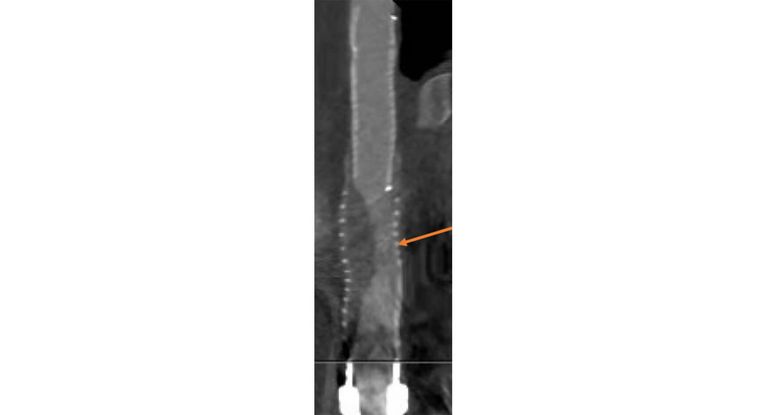

CT: LVAD-Prothese mit Stenose (dunkler Bereich).